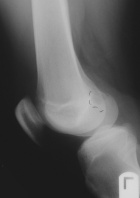

D.O. - 14 year old male with one year hx of left knee pain.

Zoom image: Radiological image Radiological image.